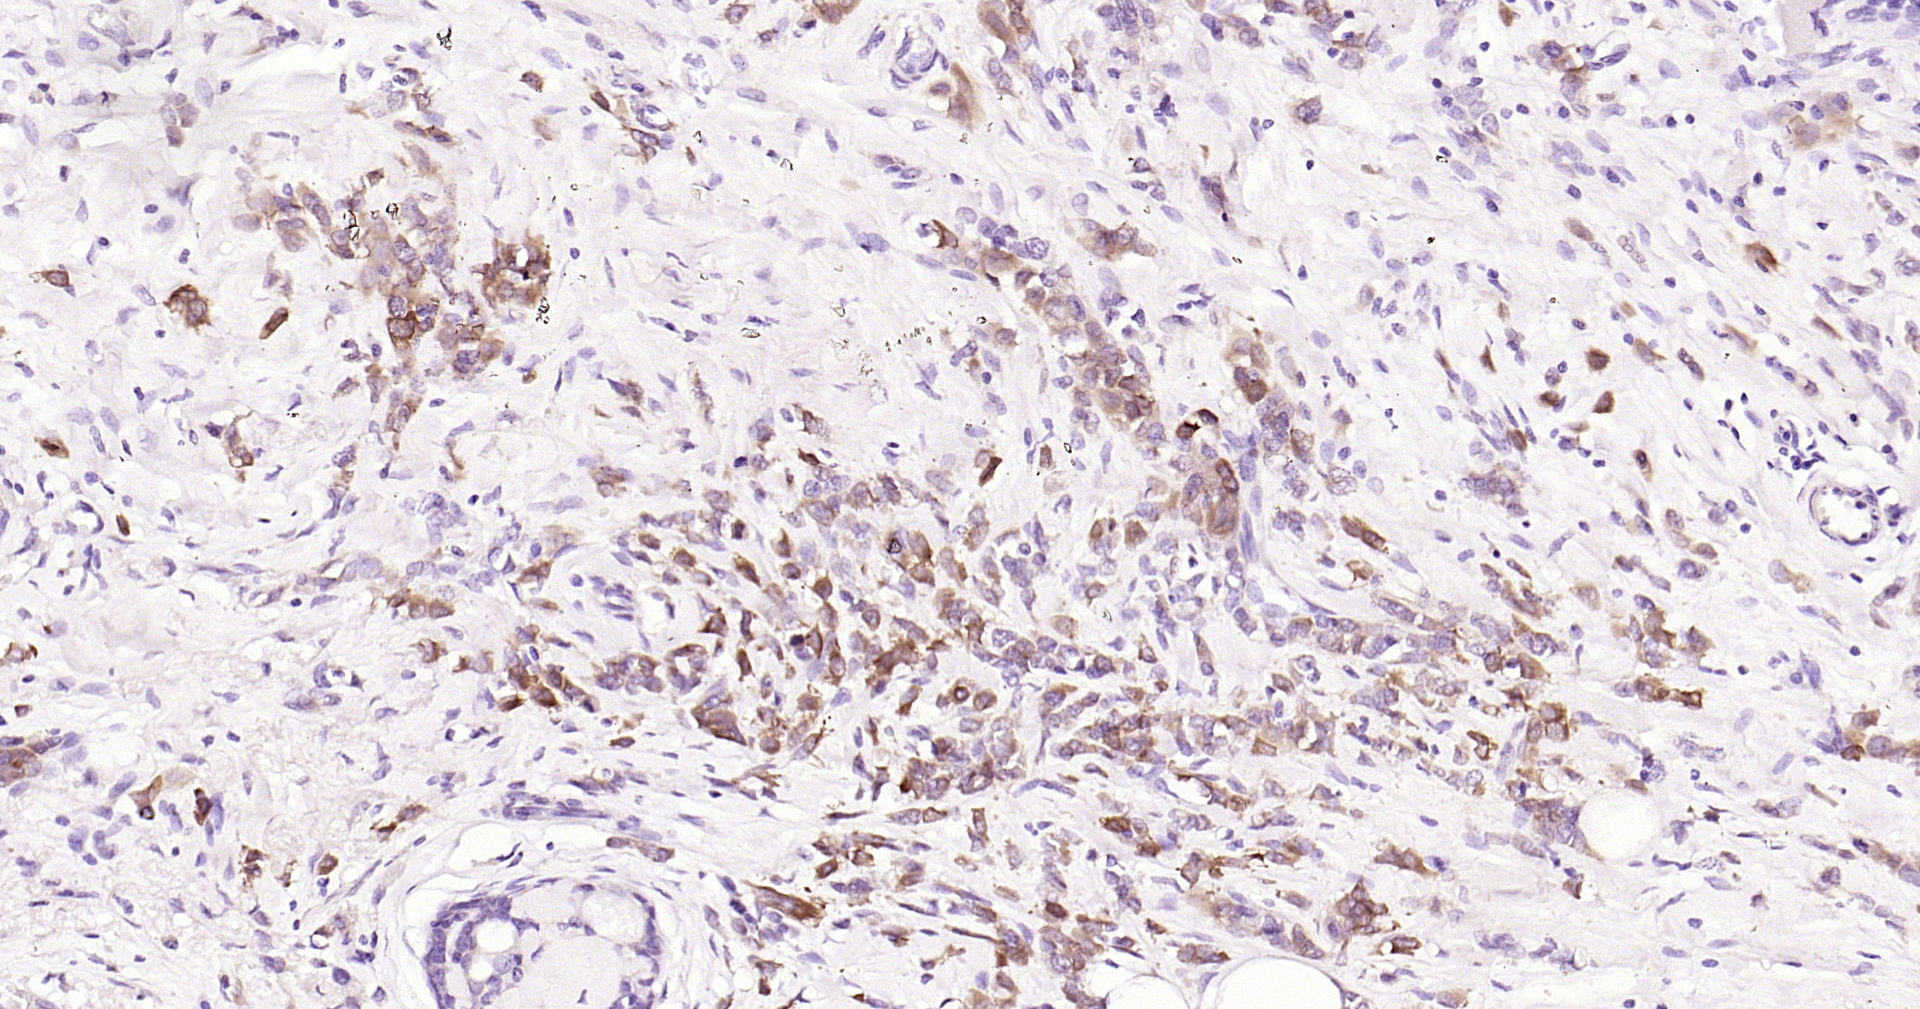

Applications IHC-P, IHC-F, IF(IHC-P)

IHC-P 1:200-1000